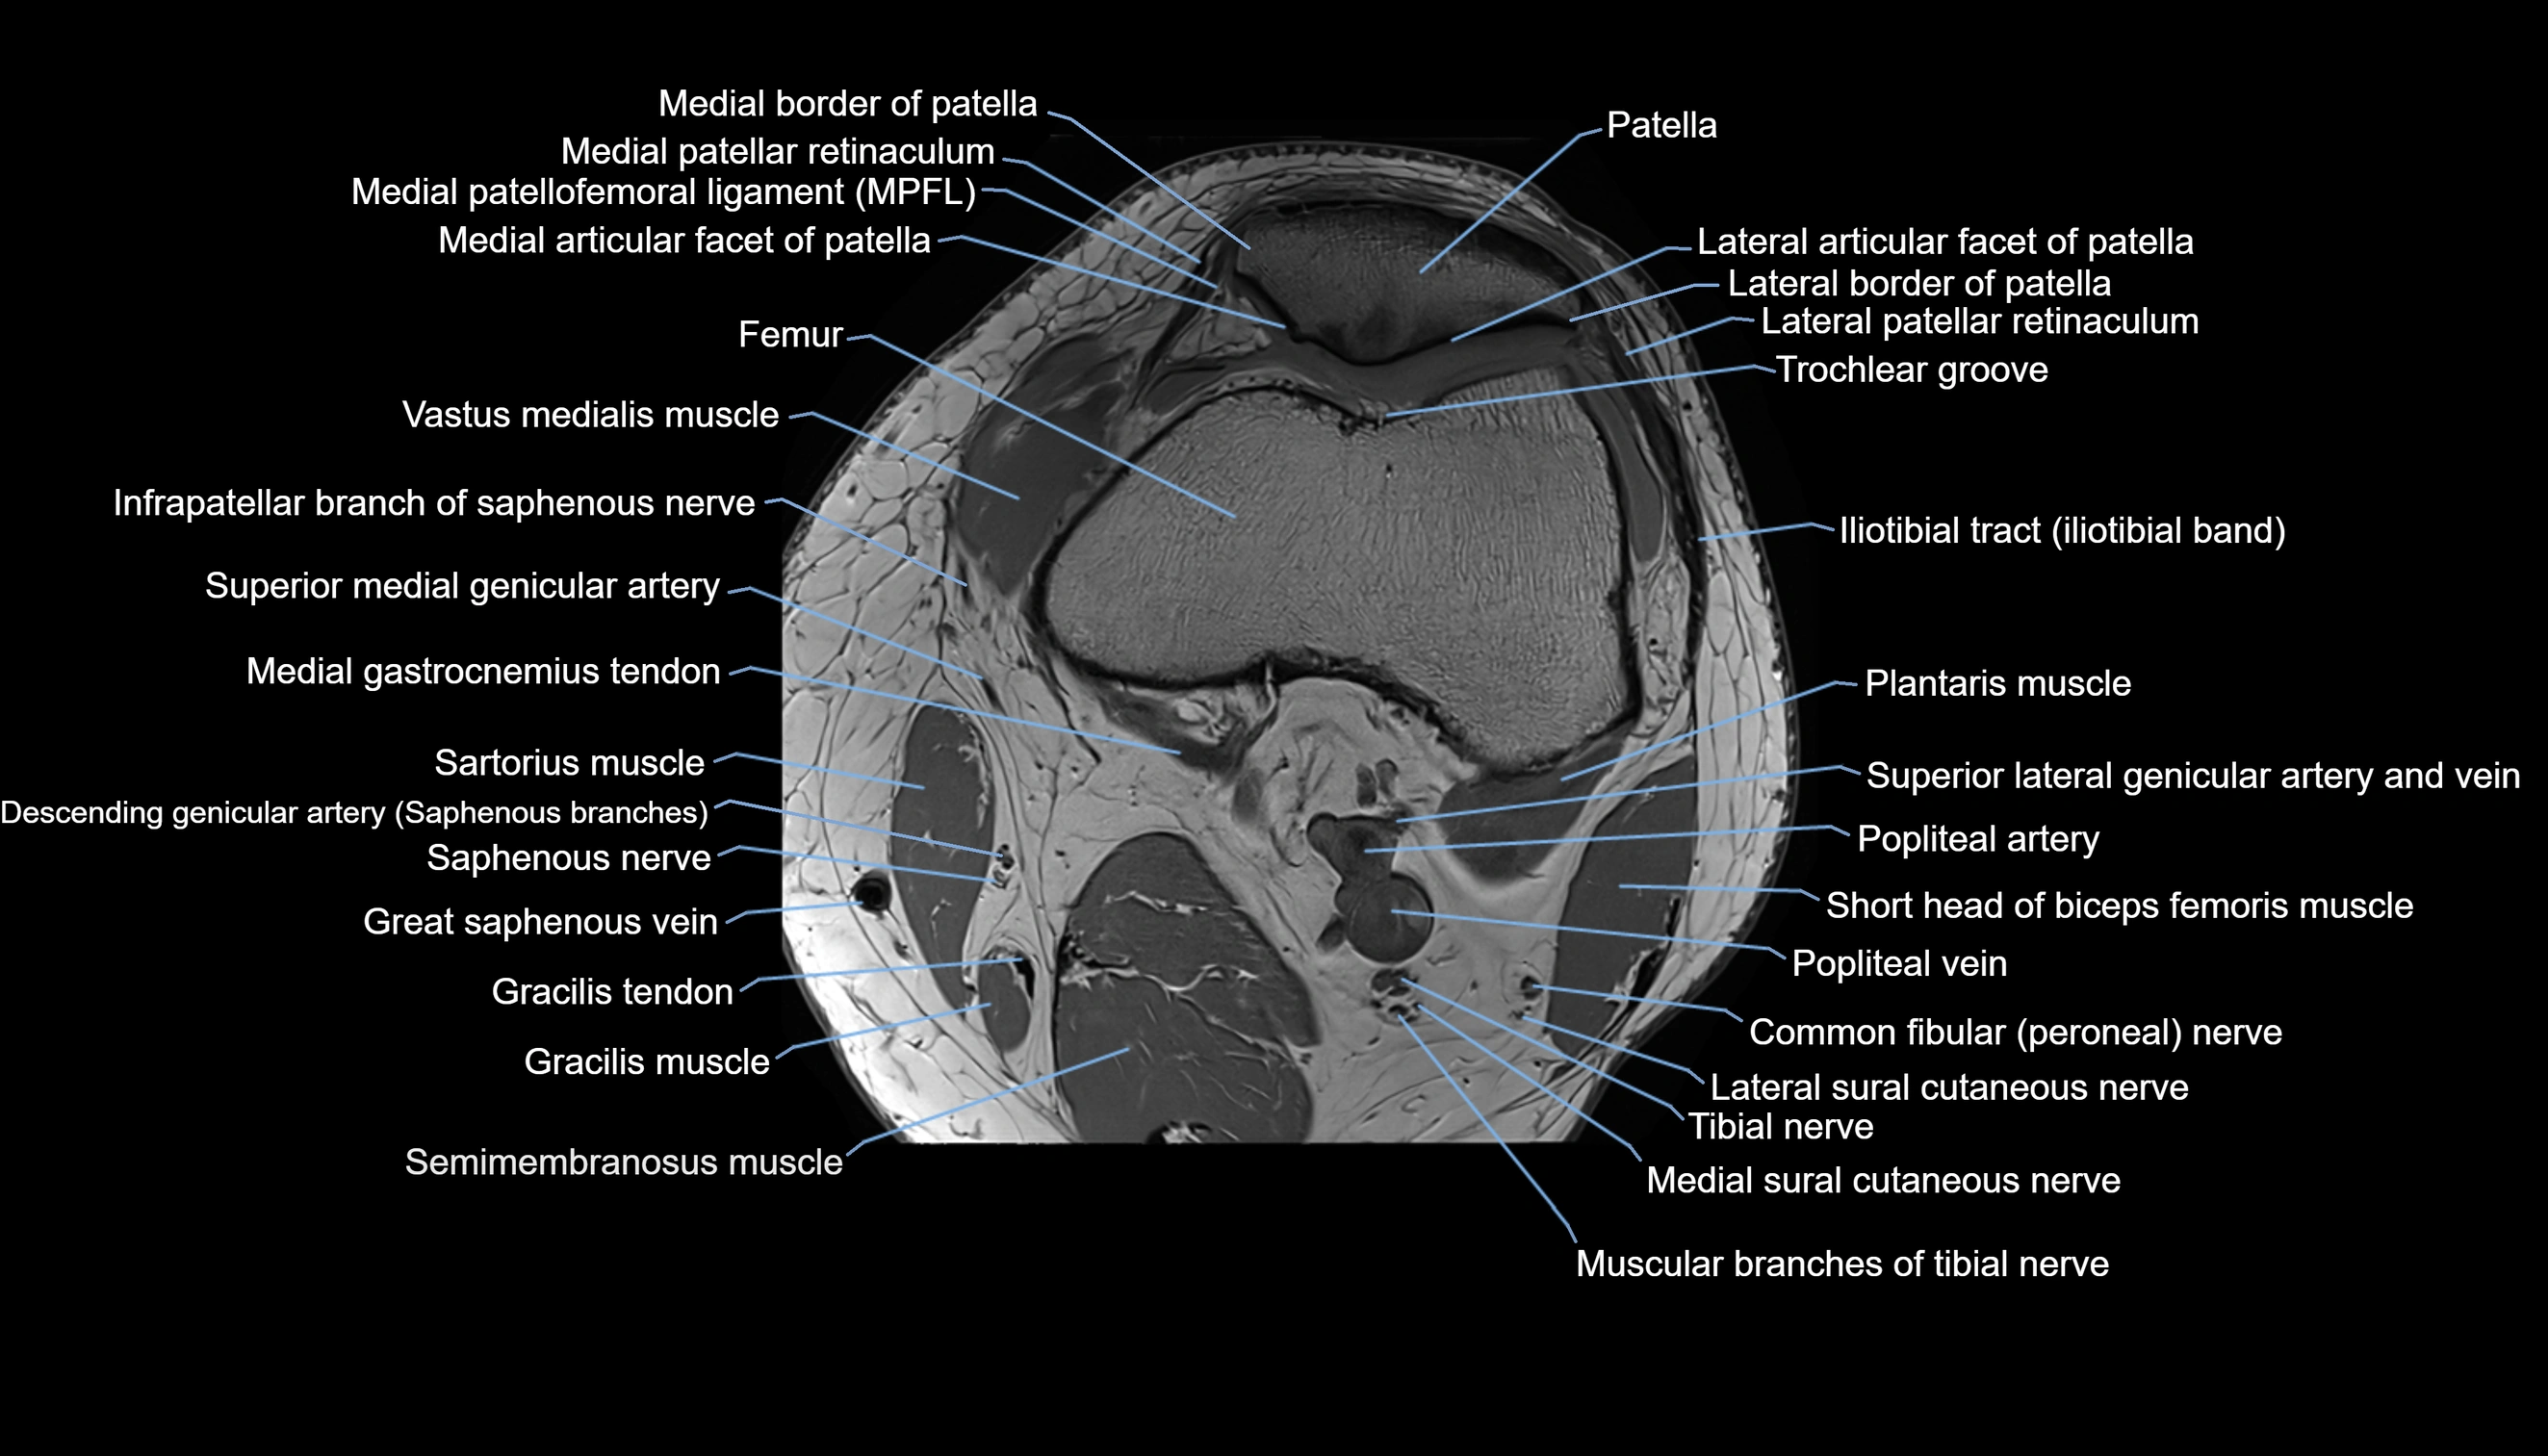

- Knee Joint

- Lateral articular facet of patella

- Lateral border of patella

- Lateral patellar retinaculum

- Lateral patellofemoral ligament

- Medial articular facet of patella

- Medial border of patella

- Medial patellar retinaculum

- Medial patellofemoral ligament

- Patella

- Popliteal artery

- Popliteal vein

- Vastus medialis muscle